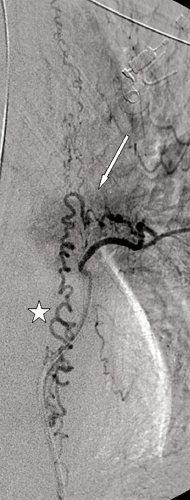

Undersökningen visade vidgade perimedullära kärl och ryggmärgsödem, fynd typiska för en spinal dural arteriovenös fistel med sekundär myelopati (Figur 3). På vårdavdelning i väntan på spinal angiografi och embolisering av fisteln försämrades patienten ytterligare och blev avföringsinkontinent. Akut spinal angiografi verifierade diagnosen, och man gjorde ett emboliseringsförsök som fick avbrytas på grund av svårigheter att nå bra kateterläge (Figur 4). Fisteln kunde slutas kirurgiskt senare samma dag.

Diagnostik. Den kliniska bilden och spinal MRT är helt avgörande för diagnosen. Okunnighet hos kliniker eller radiolog kan få som konsekvens att diagnosen ställs för sent eller inte alls, medan patienten utvecklar en obotlig parapares. De typiska fynden vid MRT är ödem och lätt svullnad av ryggmärgen torakolumbalt samt vidgade blodkärl (vener) dorsalt perimedullärt. Ödemet uppvisar hög signal centralt i ryggmärgen på T2-viktade bilder. De vida perimedullära venerna syns i cerebrospinalvätskan som slingriga strukturer med låg signal på T2-viktade bilder och hög signal på T1-viktade bilder efter intravenös kontrastmedelstillförsel.